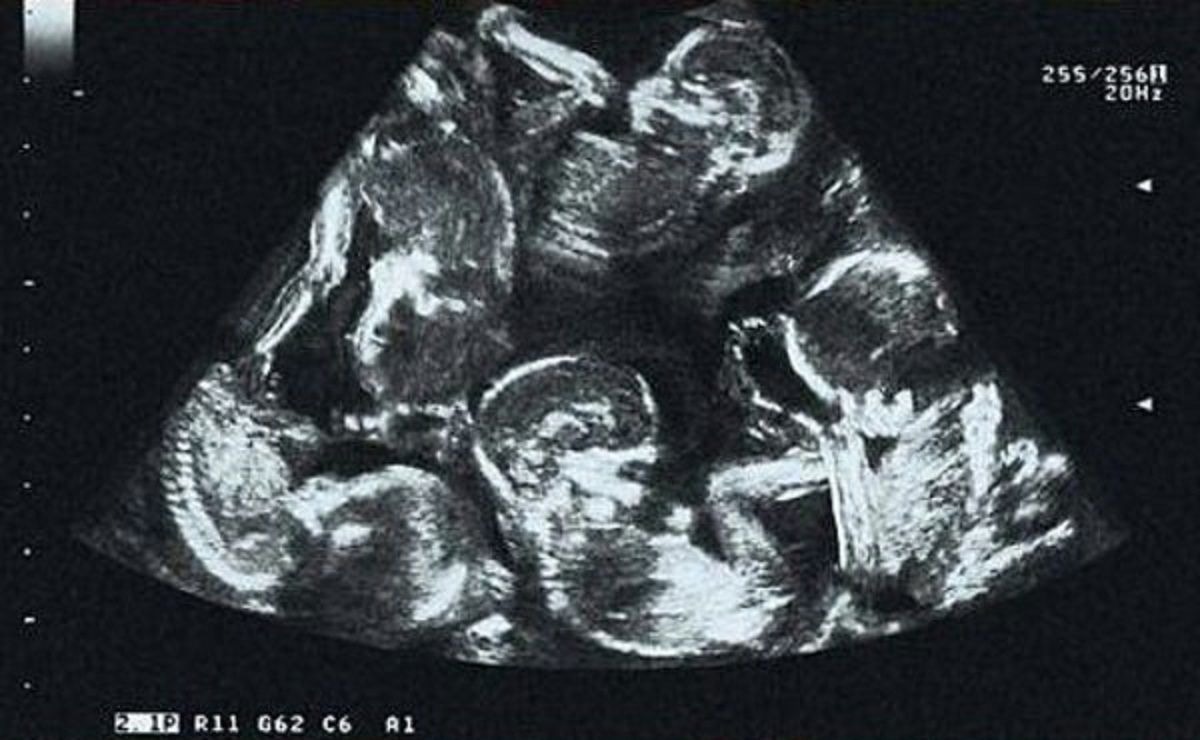

Na prvom ultrazvuku, lekari su otkrili da nosi više od jedne bebe. Par nije bio previše iznenađen — blizanci su postojali u njihovim porodicama, pa su pomislili da samo nastavljaju tradiciju. Aleksandra se pripremila za blizance, ne sluteći da joj sudbina sprema daleko veće iznenađenje.

Kasniji pregled šokirao je i lekare i roditelje. Umesto dvoje, bila su četvoro beba. To je ostavilo sve bez reči, ali najveće otkriće tek je sledilo. Novi ultrazvuk potvrdio je da Aleksandra ne očekuje četvoro, već petoro dece. Preplavljena emocijama, jedva je mogla da poveruje.